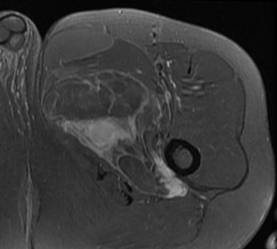

Liposarcome bien différencié. Noter la masse graisseuse, ayant une composante tissulaire (flèches) et des septas épais rehaussés après injection de gadolinium